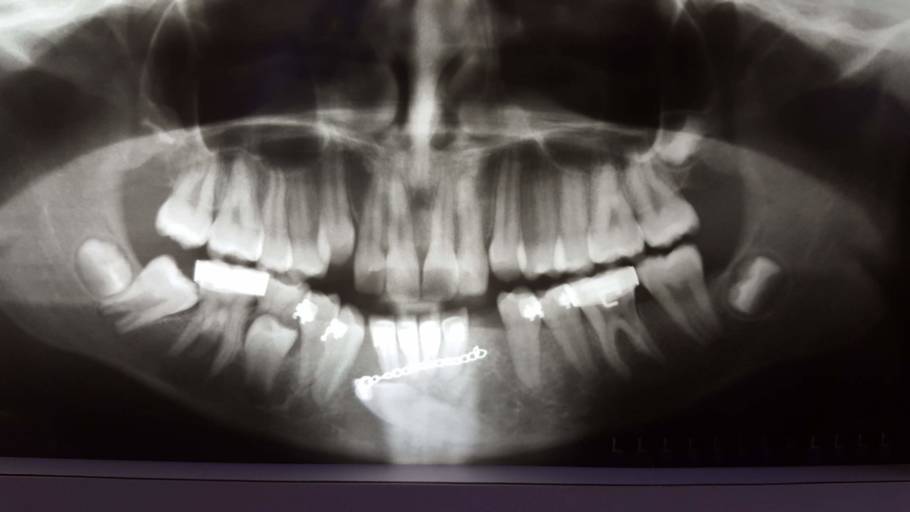

It is not abnormal for a tooth to take some time to fully erupt, especially if the primary tooth was removed prematurely. Having your dentist take an anterior radiograph at your sons next routine hygiene appointment will allow the dentist to see if there is anything blocking the eruption of the tooth. Without any dental radiographs of the anterior (front) teeth, it is hard to predict the eruption pattern. Usually it is nothing to worry about, however, an orthodontist can help the tooth fully erupt if necessary.